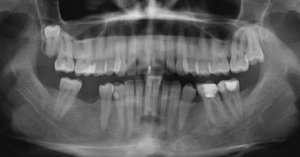

Мне необходим снимок для точного анализа и рекомендации для последующих действий.

Ваш доктор совершенно не прав, зуб необходимо удалить и как можно раньше, так как на контакте с семеркой наблюдается небольшое воспаление. Обратитесь к хирургу на удаление данного зуба, хочу отметить, что хирург должен быть другим (не тот кто рекомендовал подождать) и с навыками удаления данных зубов, чтобы избежать нежелательных последствий.